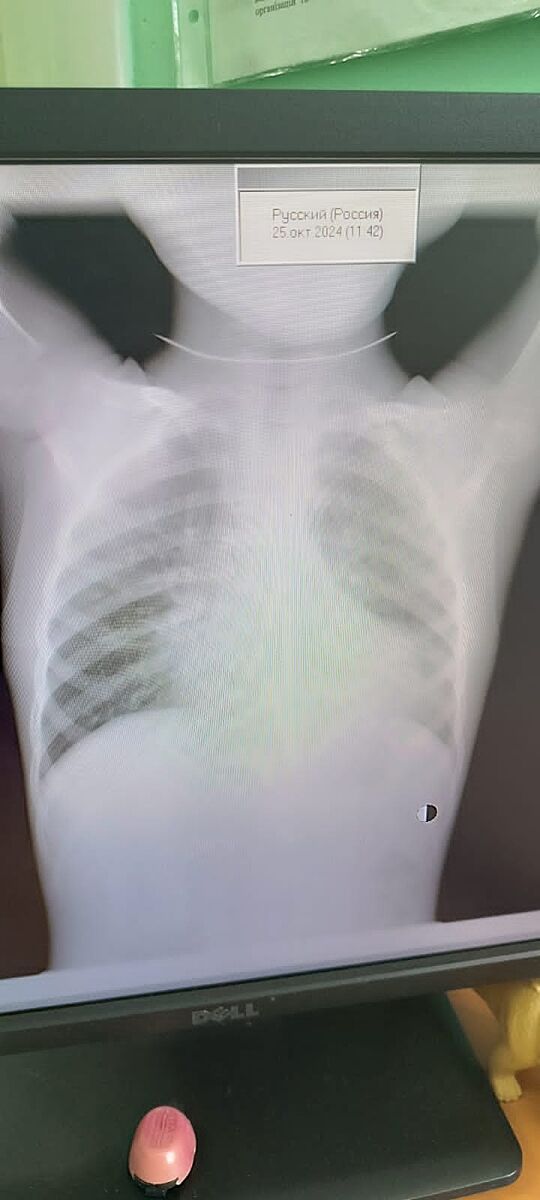

Дитині сьогодні зробили рентген,але розшифрують в понеділок. Можливо тут є лікарі, які зможуть сказати чи є запалення? Дякую.

Сложно сказать, снимок экрана не качественный. Вроде нет, смущает только один участок, но там размыто

Ще додам. Можливо, педіатр саме в тій ділянці, що мені не подобається, чула ослаблене дихання, і тоді так, для неї це не просто неякісний знімок, вона побачила підтвердження